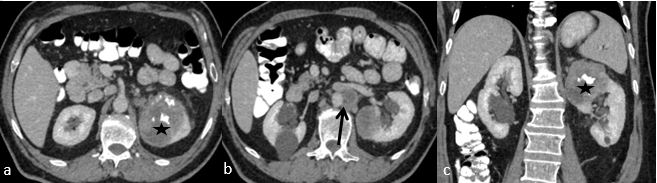

A 61-year old male referred to the urology clinic with a palpable mass in the lower left abdomen and hematuria. A contrast-enhanced CT scan revealed a heterogeneous peripherally enhanced tumor with a central hypovascular area (Figures 1 and 2); clinicoradiologically RCC was suspected and left radical nephrectomy was performed. Grossly, a well-circumscribed solid, beige tumor measuring 7 x 6 x 7cm, located in the upper pole of the left kidney with variegated areas where extensive bony hard calcification were noted (Figure 3). Sections showed a biphasic tumor, having epithelial tumor cells arranged in lobules, sheets and vague nodular pattern separated by fibrovascular septa, which were histomorphologically in favor of CRCC. Large proportion of sarcomatoid areas, dystrophic calcification and lacy malignant osteoid intermingled with malignant spindle cells (osteosarcoma component) were also noted (Figure 4). Large areas of hemorrhage and coagulative necrosis were present. Epithelial tumor cells were immunoreactive for CK7 and E-cadherin and immunonegative for CD10 and Vimentin (Figure 5). The sarcomatoid areas were immunopositive for Vimentin. There were perinephral tumor deposits, lymph node metastasis and perineural invasion. The final diagnosis was given as CRCC with sarcomatous differentiation containing osteosarcoma component.

Fig. 1. CECT abdomen, axial (a, b) and coronal (c) images showing heterogeneously enhancing mass (asterix) at upper pole of left kidney with calcification and necrosis. Enlarged lymph nodes in left para-aortic area (black arrow).